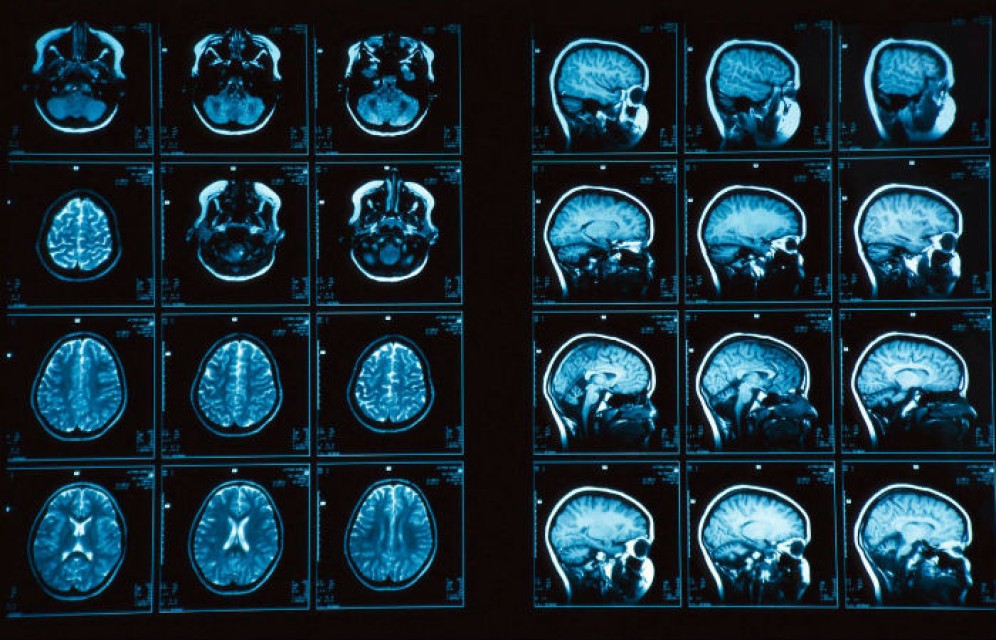

У людей, которые легко идут на финансовые риски и спокойно их переносят, обнаружена физиологическая особенность строения мозга. Таковы данные исследования ученых их американского Университета Пенсильвании, опубликованные в журнале Neuron.

Науке ранее было известно, что связи между миндалиной и префронтальной корой головного мозга влияют на развитие таких недугов, как депрессия и тревога. Ученые решили выяснить, как эти связи могут быть связаны с финансовым успехом.

Выяснилось, что более спокойно относящиеся к риску и его последствиям имеют лучшие функциональные связи между миндалиной и префронтальной корой. Также более склонные к риску имели большее количество серого вещества, сообщает "Лента.ру".